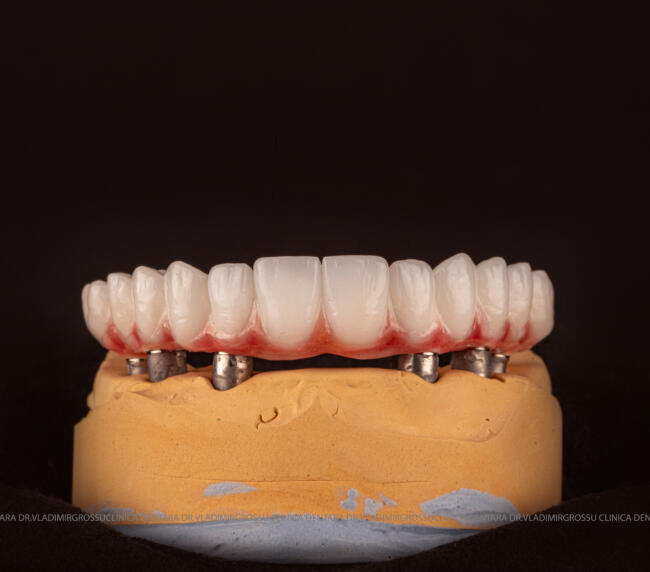

Pentru protezarea definitivă:

- Șase abutment-uri permanente pe multiunit-uri;

- Proteză definitivă realizată din metaloceramică sau zirconiu, cu 12-14 unități (soluția recomandată).

- Posibilitatea realizării unei proteze cu 12-14 dinți, oferind un aspect estetic natural și funcționalitate optimă.